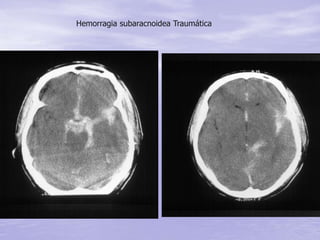

• Lesão focal - Hemorragias

– Hemorragia meningea

Hematomas: Subdural Epidural Intracerebral

• Irritação meníngea – sangue no LCR,

geralmente interhemisferica, supraselar

• Causada por ruptura de veias ou artérias

da base do crânio

• Cefaléia e/ou fotofobia

• Náusea e vômitos

• Tratamento é clinico

Hemorragia Subaracnóide

Hemorragia subaracnoidea Traumática